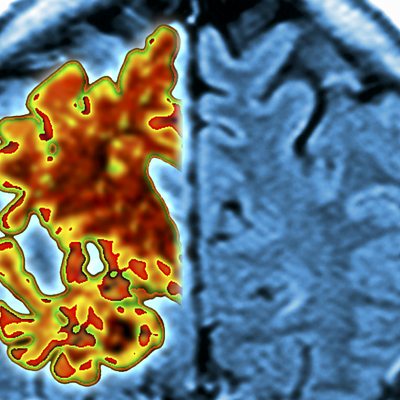

Terry from Leighton Buzzard's wife developed early on-set dementia at the age of 50.